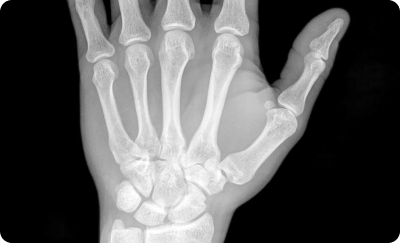

Рентгенография лучезапястных суставов в 2-х проекциях (со снимком)

Рентген лучезапястного сустава и кисти представляет собой метод визуализации этой области тела с использованием небольшой дозы ионизирующего излучения.

Рентген костей кисти и запястья – это быстрый безболезненный метод диагностики различной патологии костей и суставов дистального отдела верхней конечности.